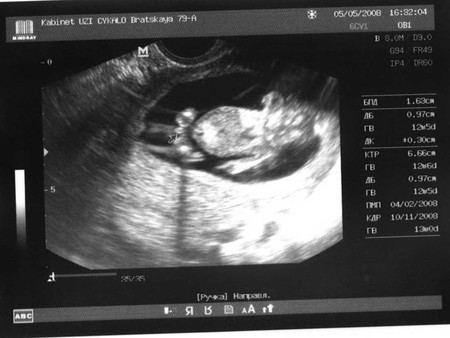

Как и обещала!!! Первое ФОТО МОЕГО МАЛЫША!!!!

моя БЕРЕМЕННОСТЬДевочки вот мой МАЛЫШ!!!! Ну что видно что ЭТО МАЛЬЧИК???? Мне кажется через чур!!!!!

прикольно:))) А нам не сказали:( Рановато говорят, вот если только трансвагинальным, а зачем? Кто есть тот и наш:) А тебя я поздравляю, ведь это здорово так рано пол узнать, и ждать именно сына!

ой, какая прелесть))) у меня тоже мальчик))) так же на узи повернулся и все показал)))) поздравляю!))

Поздравляю!!! Я тоже 2 дня назад делала УЗИ. Нам 12 неделек, но кто там мне не сказали. Я просто дико хочу мальчишечку.... Здоровья вам!!